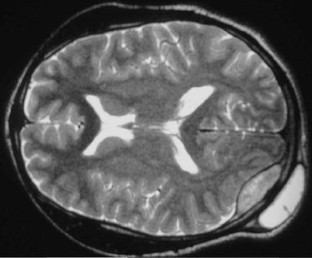

Calvarial tuberculosis: an unusual presentation (2007: 8b)

We describe a case of calvarial tuberculosis with an associated extra-dural collection. This presentation has rarely been reported in the literature and the magnetic resonance imaging features are not well documented.

Fig. 1